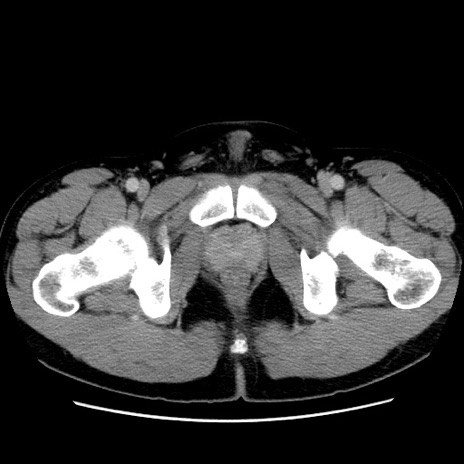

症例4(横断像)

【症例】30歳代男性

【主訴】腹痛、嘔吐

【現病歴】昨晩から突然の腹痛あり、その後嘔吐、軟便も出現。腹痛が改善しないため救急搬送となる。2日前にしめ鯖の食事歴あり。

【身体所見】意識清明、苦悶様、BP 135/90mmHg、BT 35.7℃、腹部:平坦、やや硬、心窩部〜臍部に自発痛、圧痛あり、筋性防御+、反跳痛-

【データ】WBC 8100、CRP 0.57